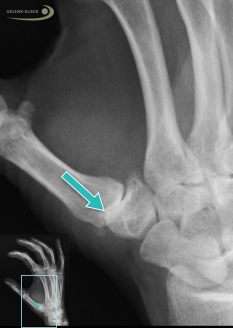

Röntgenbild einer Arthrose des Daumensattelgelenks: Der verschmälerte Gelenkspalt (Pfeil) ist deutlich sichtbar. © Gelenk-Klinik

Patienten mit Rhizarthrose haben Probleme beim Aufschrauben von Flaschen oder beim Umdrehen des Schlüssels in einem Schloss. Der Daumen fühlt sich – auch aufgrund der zunehmenden Gelenkfehlstellung im Daumensattelgelenk – instabil und wackelig an. Er ist bei Rhizarthrose nicht mehr im Daumensattelgelenk zentriert. Die Beweglichkeit des Daumen ist dabei in der Regel nicht eingeschränkt.

- Röntgendiagnose: Verschmälerung des Gelenkspaltes, Osteophyten, Sklerosierung